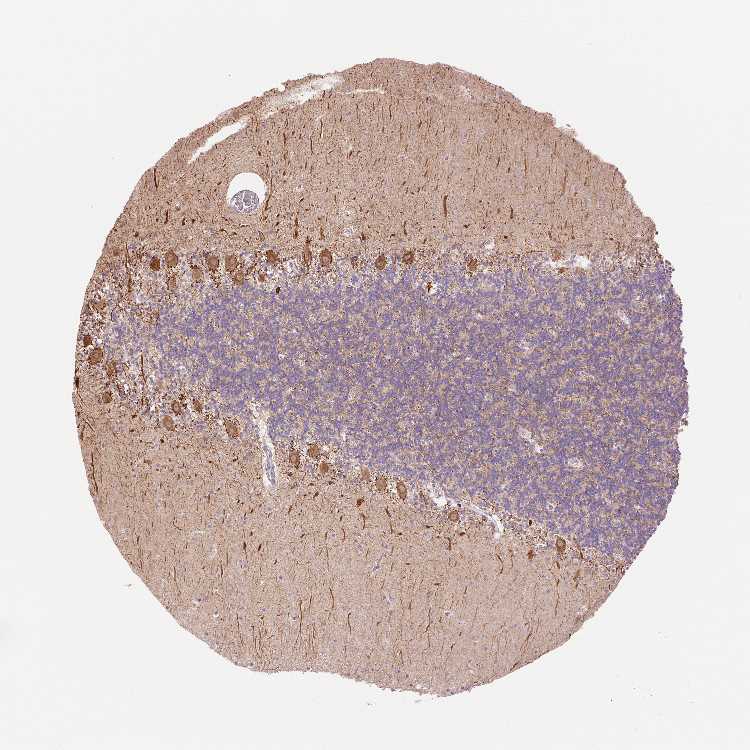

BRAIN CEREBELLUM Show tissue menu

CEREBELLUM - Antibody stainingi

Antibody staining in the annotated cell types in the current human tissue is reported as not detected, low, medium, or high, based on conventional immunohistochemistry profiling in selected tissues. This score is based on the combination of the staining intensity and fraction of stained cells.

Each image is clickable and will lead to virtual microscopy that enables deeper exploration of all samples and also displays staining intensity scores, fraction scores and subcellular localization as well as patient and tissue information for each sample.

Antibody HPA064091

Bergmann glia - cytoplasm/membrane Not detected

Bergmann glia - nucleus Not detected

GLUC cells - cytoplasm/membrane Not detected

GLUC cells - nucleus Not detected

Purkinje cells - cytoplasm/membrane Low

Purkinje cells - dendrites High

Purkinje cells - nucleus Not detected

Granular cells - cytoplasm/membrane Not detected

Granular cells - nucleus Not detected

Molecular layer - neuropil Not detected

Molecular layer cells - cytoplasm/membrane Not detected

Molecular layer cells - nucleus Not detected

Processes in granular layer High

Processes in molecular layer Not detected

Processes in white matter High

Synaptic glomeruli - capsule Not detected

Synaptic glomeruli - core Not detected

White matter cells - cytoplasm/membrane Not detected

White matter cells - nucleus Not detected